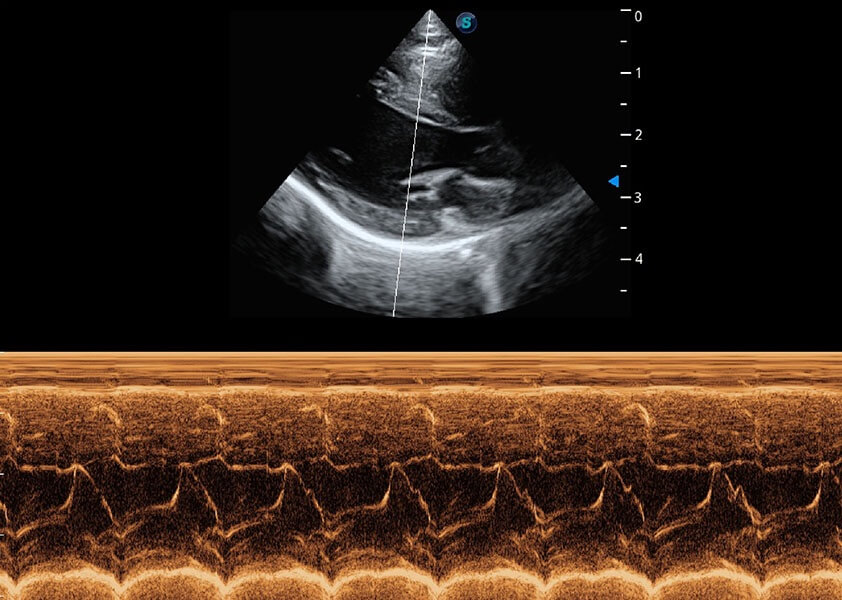

ProPet 60 作為一款高端臺(tái)式動(dòng)物超聲設(shè)備,為動(dòng)物醫(yī)生的日常診斷提供了一系列貼合動(dòng)物臨床需求、解決臨床實(shí)際問題的高級(jí)成像功能。憑借全系列高清探頭,滿足醫(yī)生對(duì)腹部、心臟、生殖、淺表、肌骨等成像的所有需求,切實(shí)幫助您提升檢查效率,提高診斷信心。